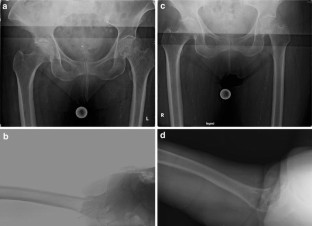

Fig. 1